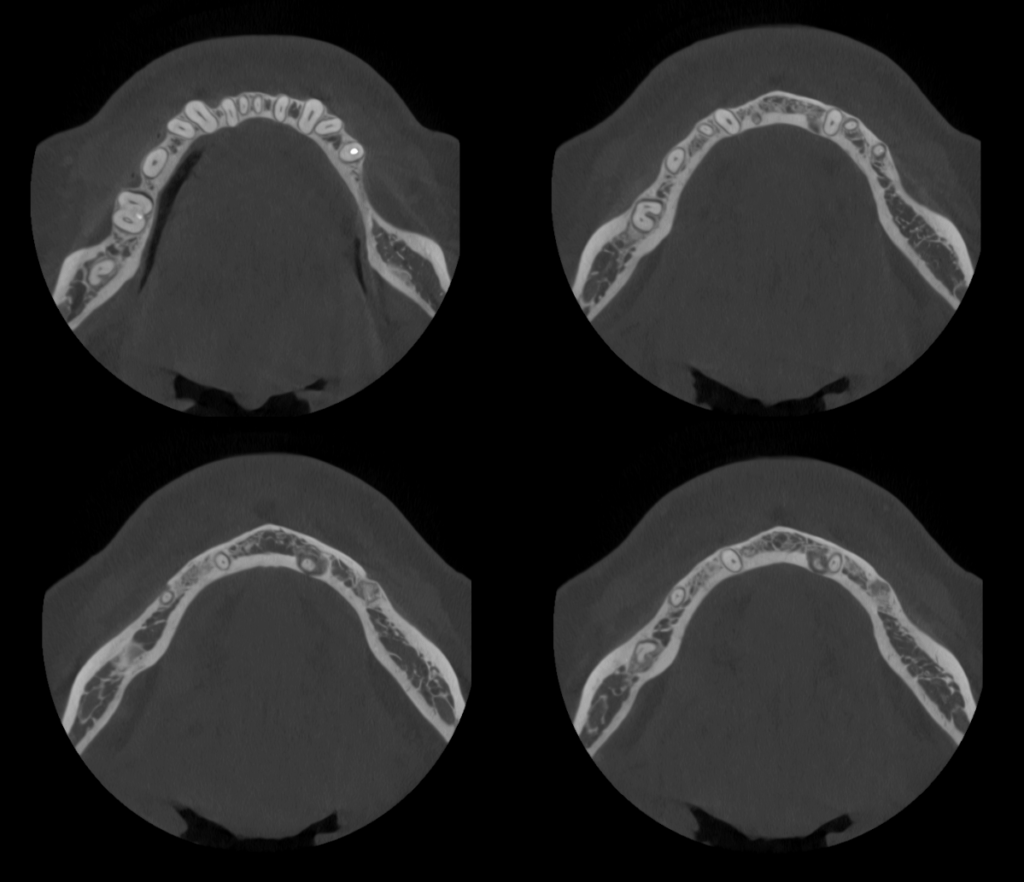

A la evaluación de la tomografía volumétrica (CBCT) en los cortes axiales (Figura 2) y transaxiales (Figura 3), se aprecia imagen mixta localiza a nivel apical de pieza 33 de limites definidos, que ocasiona adelgazamiento de tabla ósea lingual, así mismo se observa imagen mixta a nivel apical de pieza 35 y próximo a conducto dentario inferior, de limites definidos, que ocasiona adelgazamiento de tabla ósea vestibular

CORTES AXIALES